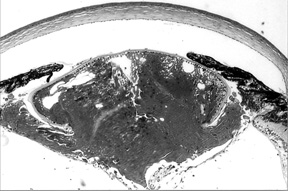

Figure 1c. Eye of To3/To3 homozygote, age 69 days.

The lens capsule has ruptured, and lens material has leaked into the abnormally small vitreous chamber.